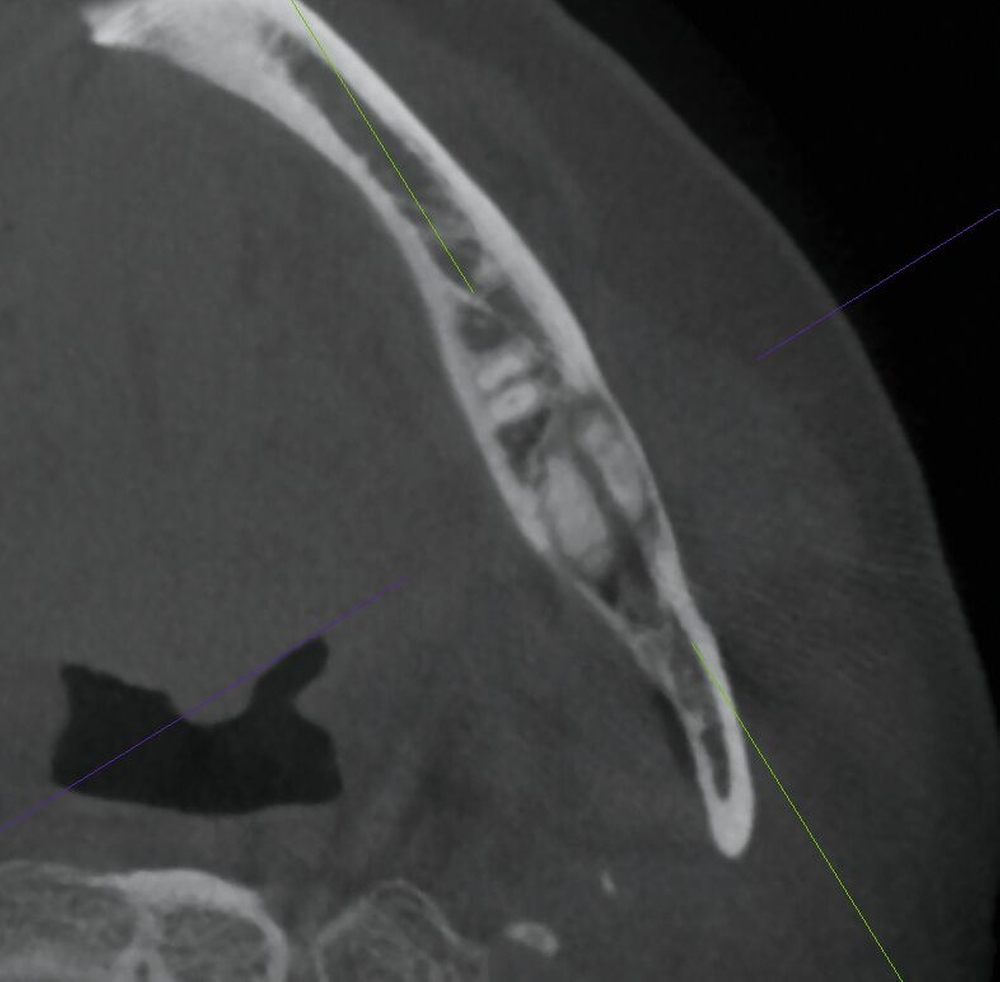

In der dreidimensionalen Bildgebung mit digitaler Volumentomografie (DVT) zeigte sich die intraossäre, scharf abgrenzbare, überwiegend homogen mineralisierte Raumforderung mit zirkulärem, hypodensem Randsaum. Der Nervus alveolaris inferior wurde durch die Läsion nach kranial verdrängt und subtotal ummauert (Abbildung 2). Zur Dignitätssicherung planten wir die vollständige Entfernung der Raumforderung unter Erhalt des Nervus alveolaris inferior in Intubationsnarkose. Eine ausgedehnte Resektion mit Unterkieferkontinuitätsdurchtrennung war aufgrund der unklaren Dignität zum Vorstellungszeitpunkt nicht indiziert.